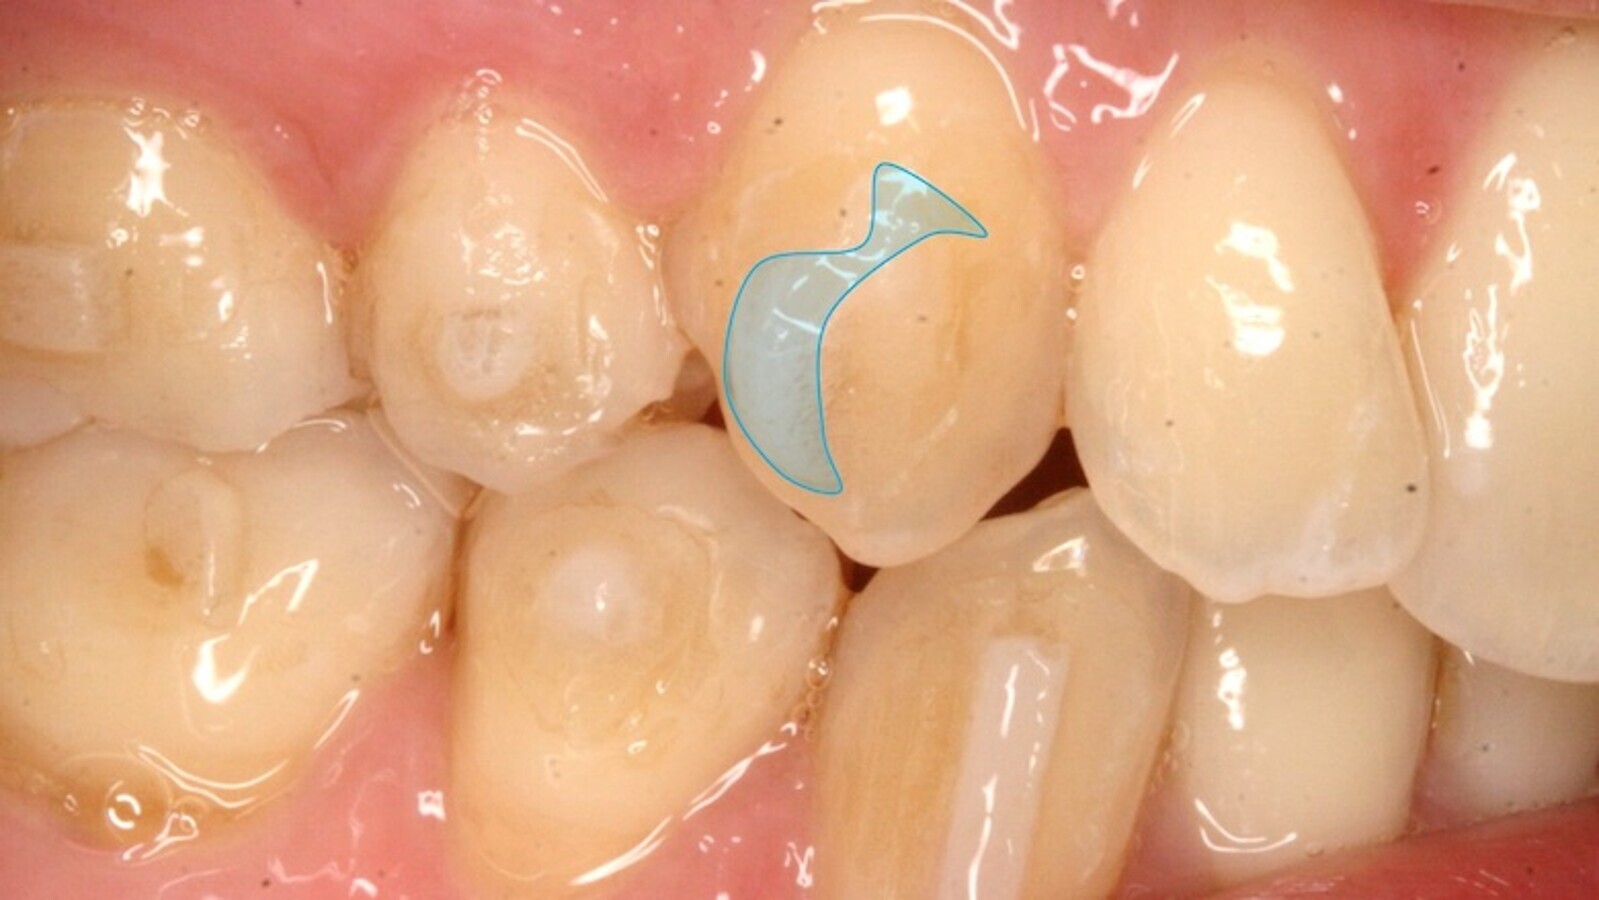

La torsión pura obedece a la relación de momento/fuerza mayor de 1 y se caracteriza porque el centro de masa se desplaza al borde incisal/oclusal y el máximo movimiento dentario se produce en el ápice; si hay movimiento o desplazamiento coronal hacia vestibular (el arco no está cinchado o ligado en distal), el movimiento no es de torsión, sino de inclinación coronal. El mecanismo de torsión en dientes posteriores es similar cuando hablamos de ortodoncia fija o de alineadores (figuras 31 a 33) y se centra, en estos últimos, en la aplicación de un par de fuerzas sobre un prisma rectangular (en la técnica multibrackets se hace con el doblado del alambre alrededor de su eje mayor o incorporando una determinada angulación en el bracket).

Figuras 31-33. El mecanismo de torsión en dientes posteriores es similar cuando hablamos de ortodoncia fija o de alineadores.

El mecanismo de torsión en dientes posteriores es similar cuando hablamos de ortodoncia fija o de alineadores.